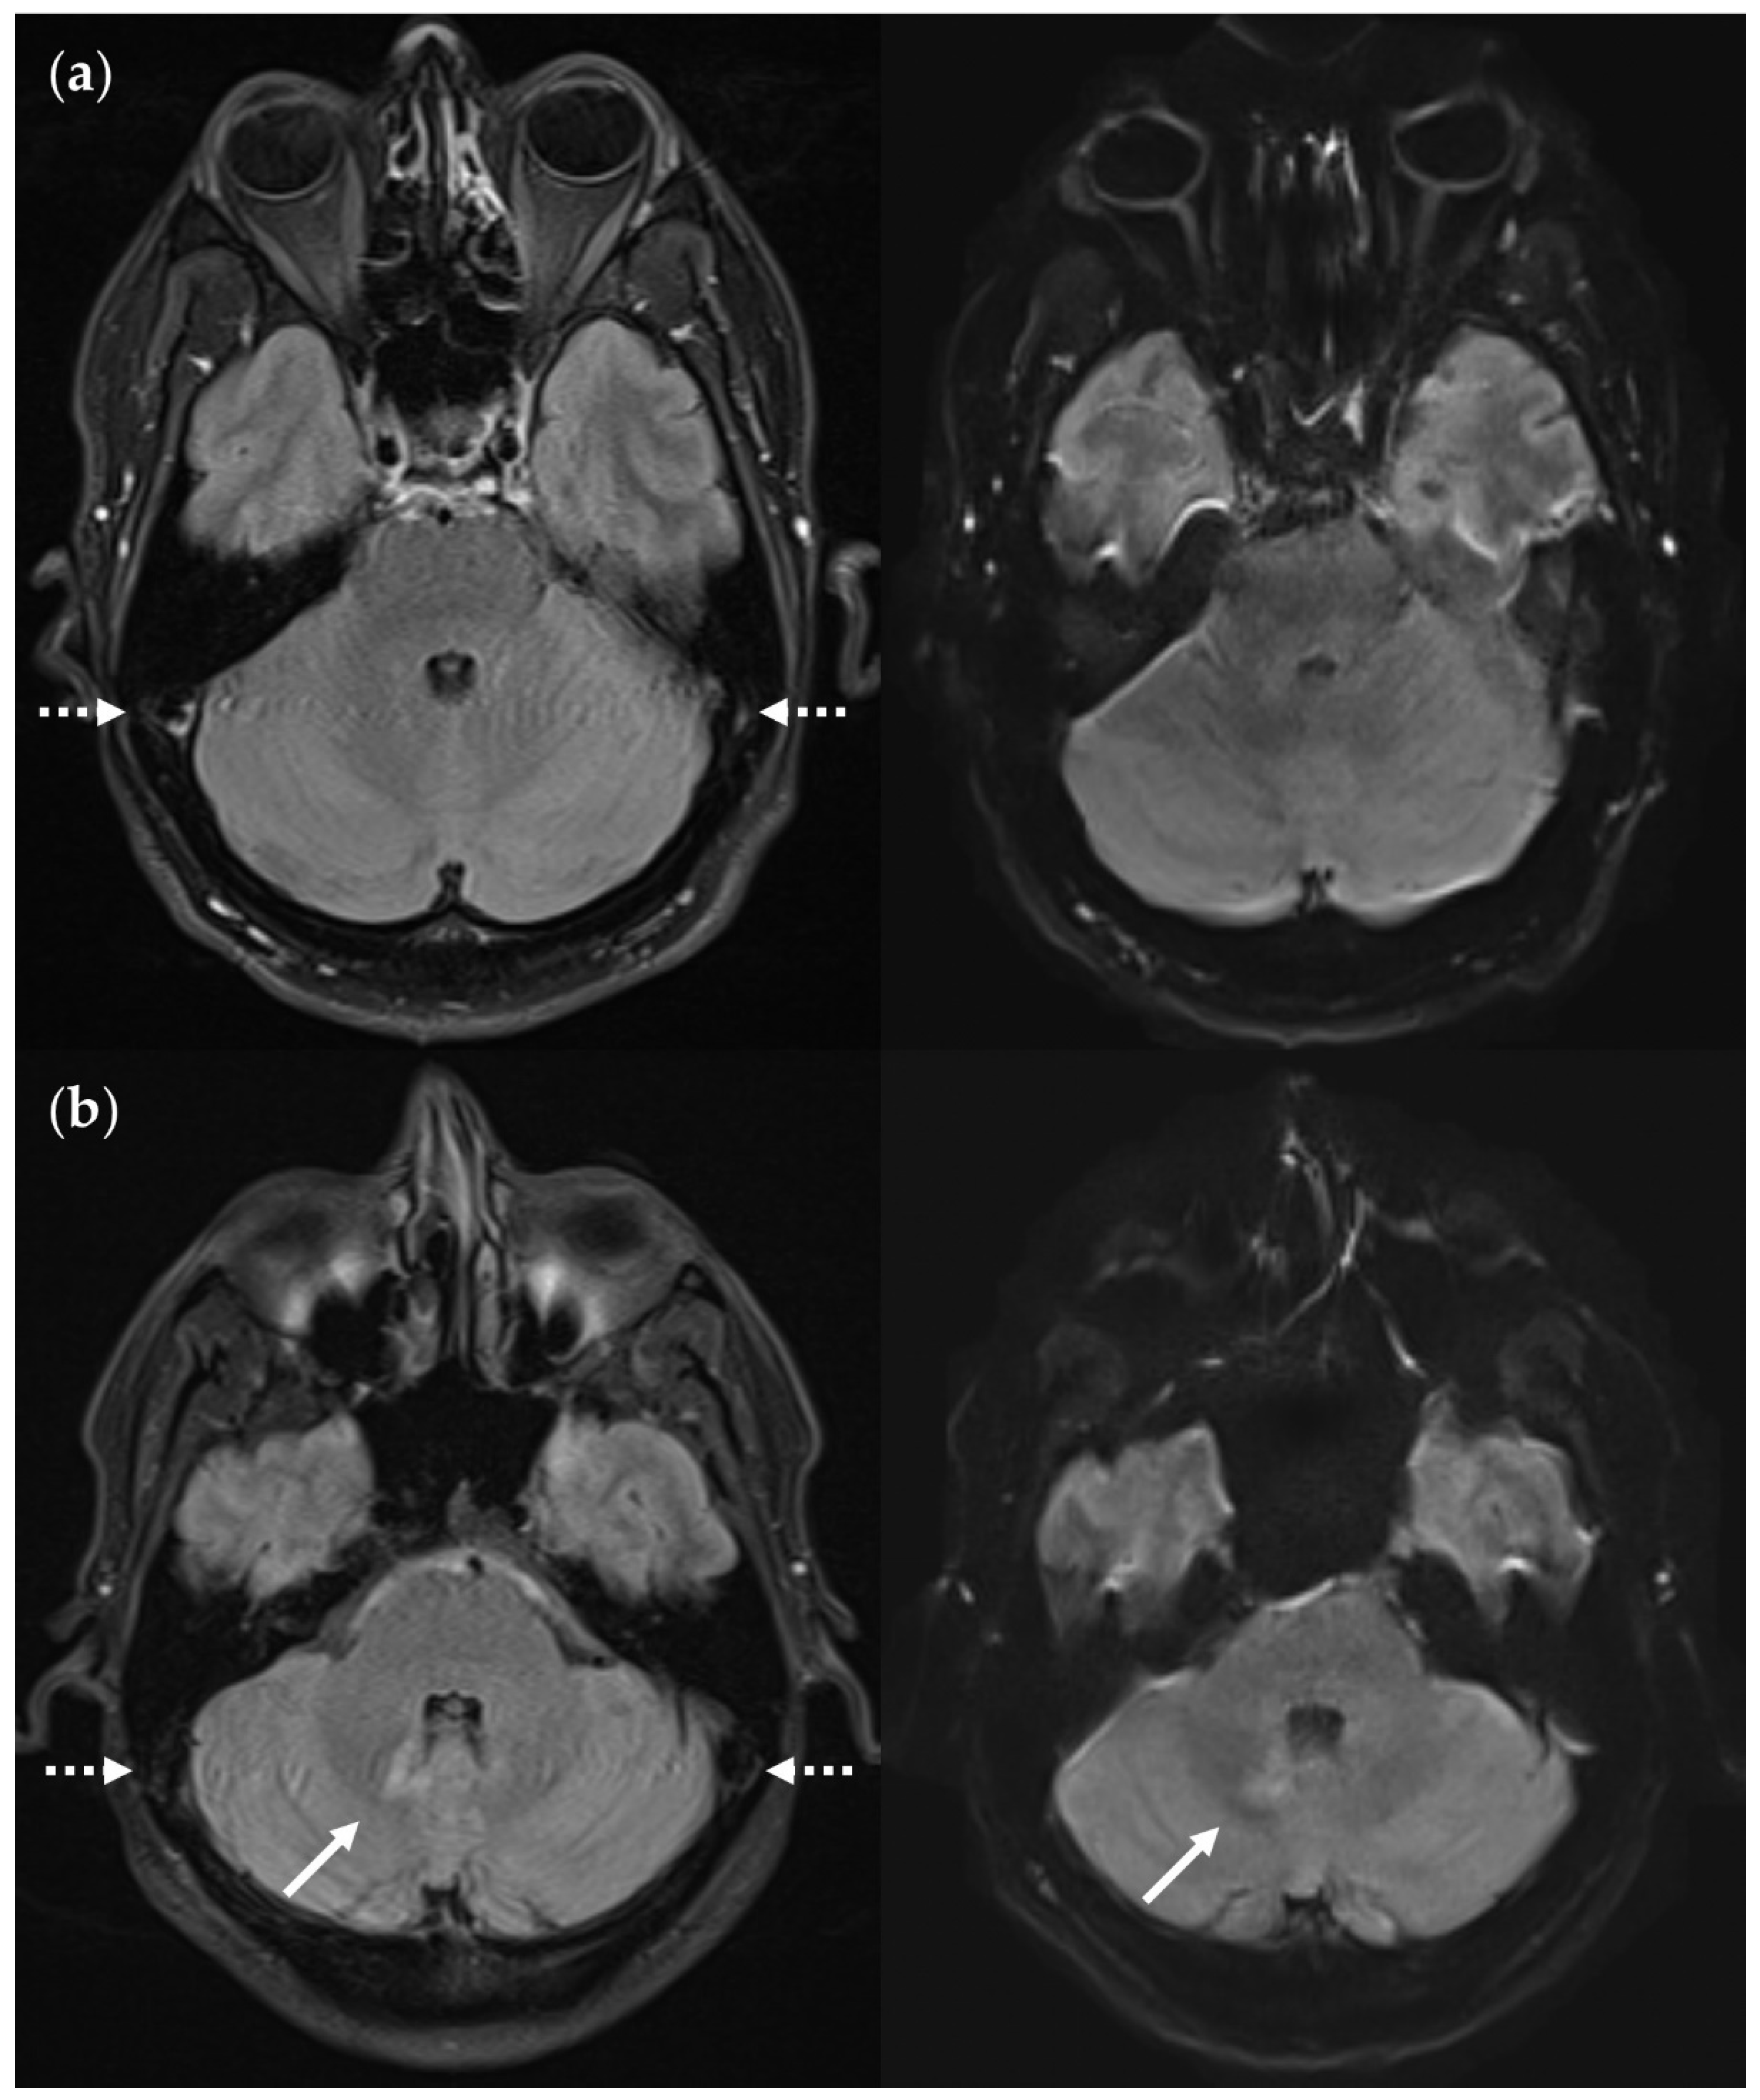

Infratentorial pulsatile flow artifacts that severely limit diagnostic information in the FLAIRUF images and the FLAIR3Da images. (a) FLAIRUF (left) and FLAIR3Da as a reference (right), cerebellum: The continuous arrows depict an inflammatory true positive lesion (approx. 4 mm × 3 mm). The dotted arrow indicates a pulsation artifact that is prone to being confused with a lesion. It was counted as a small, false positive lesion (approx. 2 mm × 1 mm). The arrowhead points to a pulsation artifact that is not likely to be confused with a lesion due to its typical location adjacent to the occipital sinus. (b) FLAIR3Da (left) and FLAIRUF as a reference (right), at the level of the pons: Top images: Typical hyperintense artifact band in the FLAIR3Da image; the arrowhead points to an intensely hyperintense spot within the artifact region that is part of the grainy texture of the artifact. Possible lesions within the artifact region would have been masked completely. Middle images: the continuous arrows show a large lesion (approx. 8 mm × 3 mm) that was misinterpreted as part of the pulsation artifact in the FLAIR3Da image. Bottom images: The dotted arrow denotes a small, false positive FLAIR3Da lesion (approx. 2 mm × 2 mm) that turned out to be part of the pulsation artifact.Note. Corresponding slices could not be positioned exactly identically owing to different slice thicknesses including slice gaps and non-parallel slice inclinations.

Figure 15.